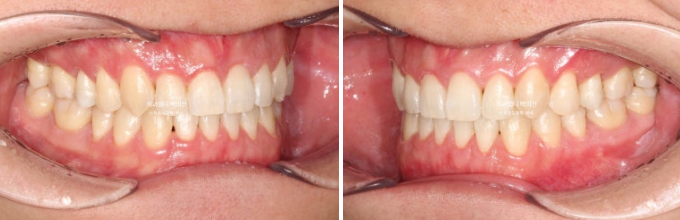

Now let’s compare before and after.

Treatment began in January 2023, and the time spent on arch expansion and waiting for bone to fill in was 6 months. The actual orthodontic treatment period while wearing Invisalign aligners was from July 2023 to March 2025, for a total of 1 year and 8 months.

In the front teeth area, once the open bite and reverse bite were corrected, a stable bite was created.